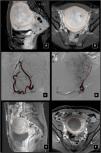

Identificar qué pacientes tendrán mejores resultados clínicos tras la EAU es difícil. En cuanto al tamaño del leiomioma, la EAU ha sido utilizada tradicionalmente para tratar leiomiomas de tamaño relativamente pequeño, habiéndose descrito casos con complicaciones en miomas más grandes (> 8 cm). Sin embargo, estudios recientes no mostraron diferencias clínicas ni tasas de complicaciones diferentes tras la EAU de miomas grandes (> 10 cm) en un total de 100 pacientes23 (fig. 5).

Leiomioma. A-B) RM de pelvis previa a la embolización. Secuencias T1 con saturación grasa después de la administración de contraste, cortes sagital (A) y axial (B) donde se observa voluminosa (> 10 cm) lesión nodular hipercaptante en fundus uterino (línea discontinua), en relación con leiomioma mural. C) Arteriografía selectiva de la AU derecha (flecha discontinua roja). D) Arteriografía superselectiva con microcatéter (flecha señalando punta del microcatéter) de la AU izquierda (línea discontinua roja) por abordaje femoral derecho. E-F) RM de pelvis control 12 meses después de EAU bilateral con partículas. Mismas secuencias (T1 saturación grasa tras contraste) cortes sagital (E) y axial (F), donde se observa disminución del tamaño e hipocaptación por necrosis del leiomioma mural (línea discontínua).

Carcinoma cérvix estadio IV. A-B) RM de pelvis en paciente con carcinoma de cérvix estadío IV. Secuencias potenciadas en T2 axial (A) y sagital (B), donde se observa masa cervical (cuadrado). La paciente acude a urgencias por metrorragia y anemización. C-D-E) Se realiza angio-TC urgente donde se observa masa necrótica con foco de extravasación de contraste en las sucesivas fases del angio-TC (círculos) fases: C) sin contraste, D) arterial y E) portal, compatible con sangrado activo en lecho tumoral (círculo). F) Arteriografía de arteria iliaca interna derecha por abordaje femoral derecho, donde se confirma foco de sangrado activo (flecha).